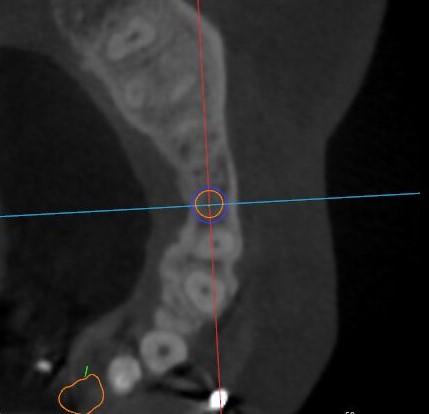

觀察患者CT,可看出患者有上頜竇粘膜囊腫,粘膜囊腫為竇內(nèi)腺體阻塞所致,視情況可有手術(shù)摘除和不予處理兩種方法,此次患者拒絕手術(shù)摘除,故需規(guī)避上頜竇位置。

冠狀面視圖

矢狀面視圖

軸狀面視圖

根據(jù)患者CT顯示,使用種植導(dǎo)航軟件設(shè)術(shù)前手術(shù)方案??紤]到患者拒絕手術(shù)摘除上頜竇囊腫等因素,此次手術(shù)選用了Straumann骨水平4.10*8.0mm的植體,植體末端位點(diǎn)設(shè)計(jì)距上頜竇底壁2mm處的同時(shí)兼顧種植方向和修復(fù)間隙,來(lái)達(dá)到理想的效果。